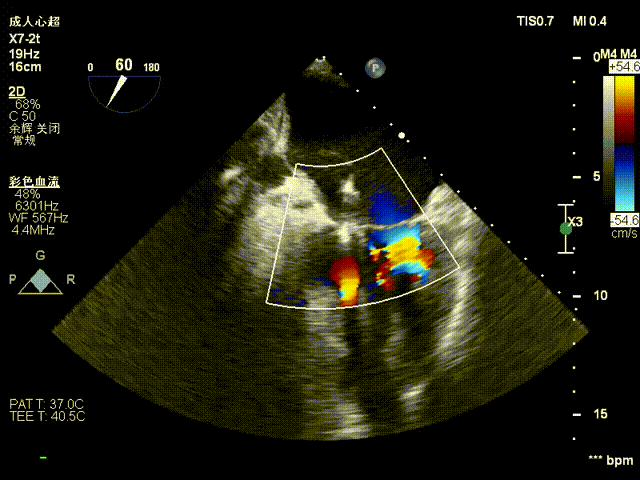

术前影像

二尖瓣后瓣腱索断裂并脱垂及关闭不全(重度)